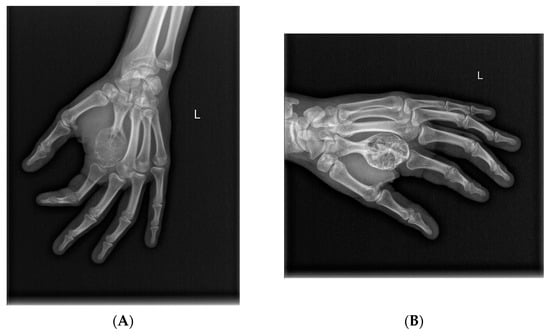

- McCarthy, C.L.; Gibbons, C.L.M.H.; Bradley, K.M.; Hassan, A.B.; Giele, H.; Athanasou, N.A. Giant cell tumour of the distal radius/ulna: Response to pre-operative treatment with short-term denosumab. Clin. Sarcoma Res. 2017, 7, 19. [Google Scholar] [CrossRef]

- Hakozaki, M.; Tajino, T.; Yamada, H.; Hasegawa, O.; Tasaki, K.; Watanabe, K.; Konno, S. Radiological and pathological characteristics of giant cell tumor of bone treated with denosumab. Diagn. Pathol. 2014, 9, 111. [Google Scholar] [CrossRef]

- Van Langevelde, K.; McCarthy, C.L. Radiological findings of denosumab treatment for giant cell tumours of bone. Skelet. Radiol. 2020, 49, 1345–1358. [Google Scholar] [CrossRef] [PubMed]

- Oguro, S.; Okuda, S.; Sugiura, H.; Matsumoto, S.; Sasaki, A.; Susa, M.; Morioka, H.; Jinzaki, M. Giant Cell Tumors of the Bone: Changes in Image Features after Denosumab Administration. Magn. Reson. Med. Sci. 2018, 17, 325–330. [Google Scholar] [CrossRef]